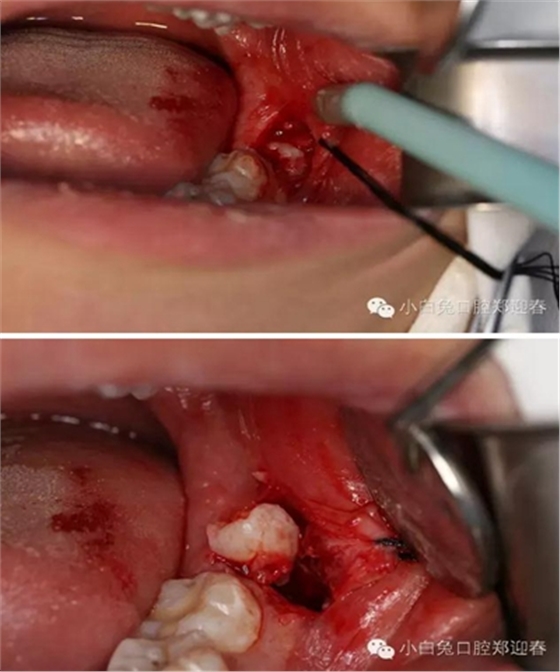

利用微創(chuàng)拔牙標(biāo)準(zhǔn)進(jìn)行阻力冠切割

切割過(guò)程對(duì)冷卻和角度的要求,一定要是水柱的噴射。

渦輪動(dòng)力切割阻力牙冠

“T”型分割近中阻力冠

分別去除近中阻力冠的頰和舌部的牙冠

順著牙長(zhǎng)軸的方向挺出牙根,這樣可以避免因?yàn)檠栏D(zhuǎn)對(duì)神經(jīng)管的影響。

處理牙槽窩,保留完整的牙槽骨形態(tài)。

置入膠原蛋白,縫合創(chuàng)口。